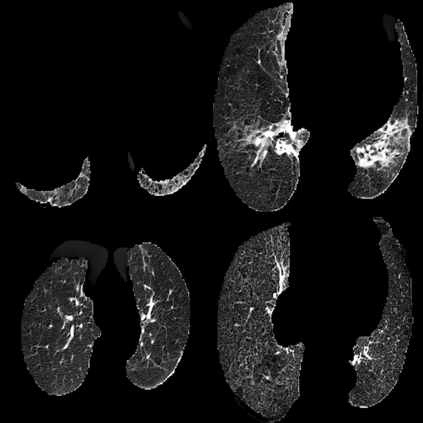

In the field of medical imaging, particularly in tasks related to early disease detection and prognosis, understanding the reasoning behind AI model predictions is imperative for assessing their reliability. Conventional explanation methods encounter challenges in identifying decisive features in medical image classifications, especially when discriminative features are subtle or not immediately evident. To address this limitation, we propose an agent model capable of generating counterfactual images that prompt different decisions when plugged into a black box model. By employing this agent model, we can uncover influential image patterns that impact the black model's final predictions. Through our methodology, we efficiently identify features that influence decisions of the deep black box. We validated our approach in the rigorous domain of medical prognosis tasks, showcasing its efficacy and potential to enhance the reliability of deep learning models in medical image classification compared to existing interpretation methods. The code will be publicly available at https://github.com/ayanglab/DiffExplainer.